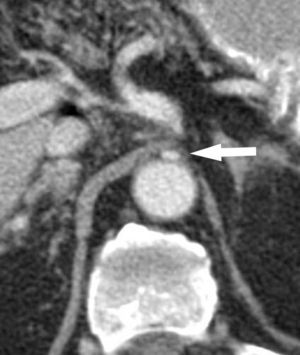

Reconstrucción en plano sagital (TCMD) en inspiración forzada. Impronta del ligamento arcuato mediano sobre el origen del tronco celíaco, estenosando su luz y dándole la típica morfología en “gancho”, con dilatación posestenótica asociada (flecha): síndrome del ligamento arcuato mediano. (Tomado de Soliva Martínez D, Fernández Iglesias P, Belda González I, Martínez Yunta JA, Hernández Muñoz L, Blanco López ME. Hallazgos poco conocidos en el síndrome del ligamento arcuato mediano. 10.1594/seram2014/S-0407).